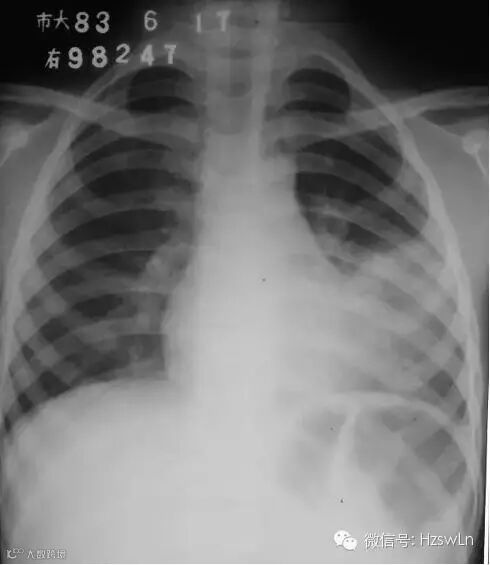

导读:基本情况:男性,12岁咳嗽、发热检查方法:胸部后前位片描述:左侧中下肺野中内带大片高密度影,密度不均,边缘模

基本情况:

男性,

12

岁咳嗽、发热

检查方法:

胸部后前位片

描述:

左侧中下肺野中内带大片高密度影,密度不均,边缘模糊。

初步诊断

:左下肺大叶性肺炎